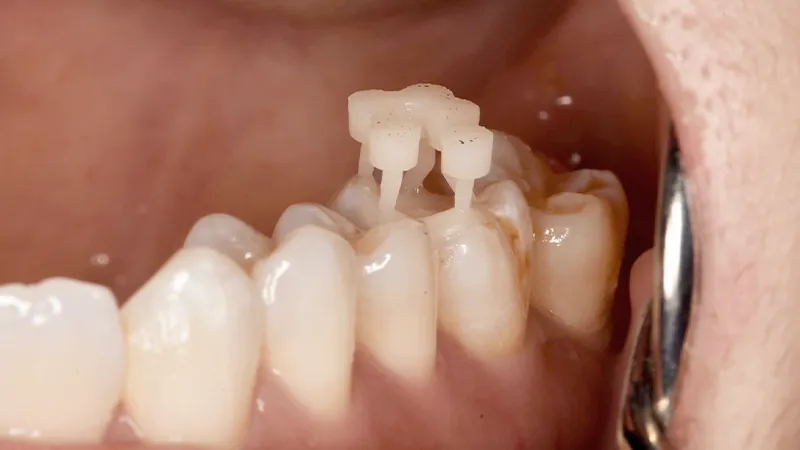

4. Characterisation and bonding:

- Staining was performed using Empress Direct mixed with OT2 to achieve seamless integration with natural dentition.

- The onlay was bonded using a total-etch adhesive technique, ensuring maximum retention and durability.

The final restoration exhibited excellent adaptation, aesthetics, and functional integrity. The printed hybrid ceramic onlay effectively mimicked natural tooth wear characteristics while offering superior resistance to occlusal forces. The decision to avoid a deep mesial margin ensured that gingival health was maintained, preventing potential complications associated with subgingival restorations.